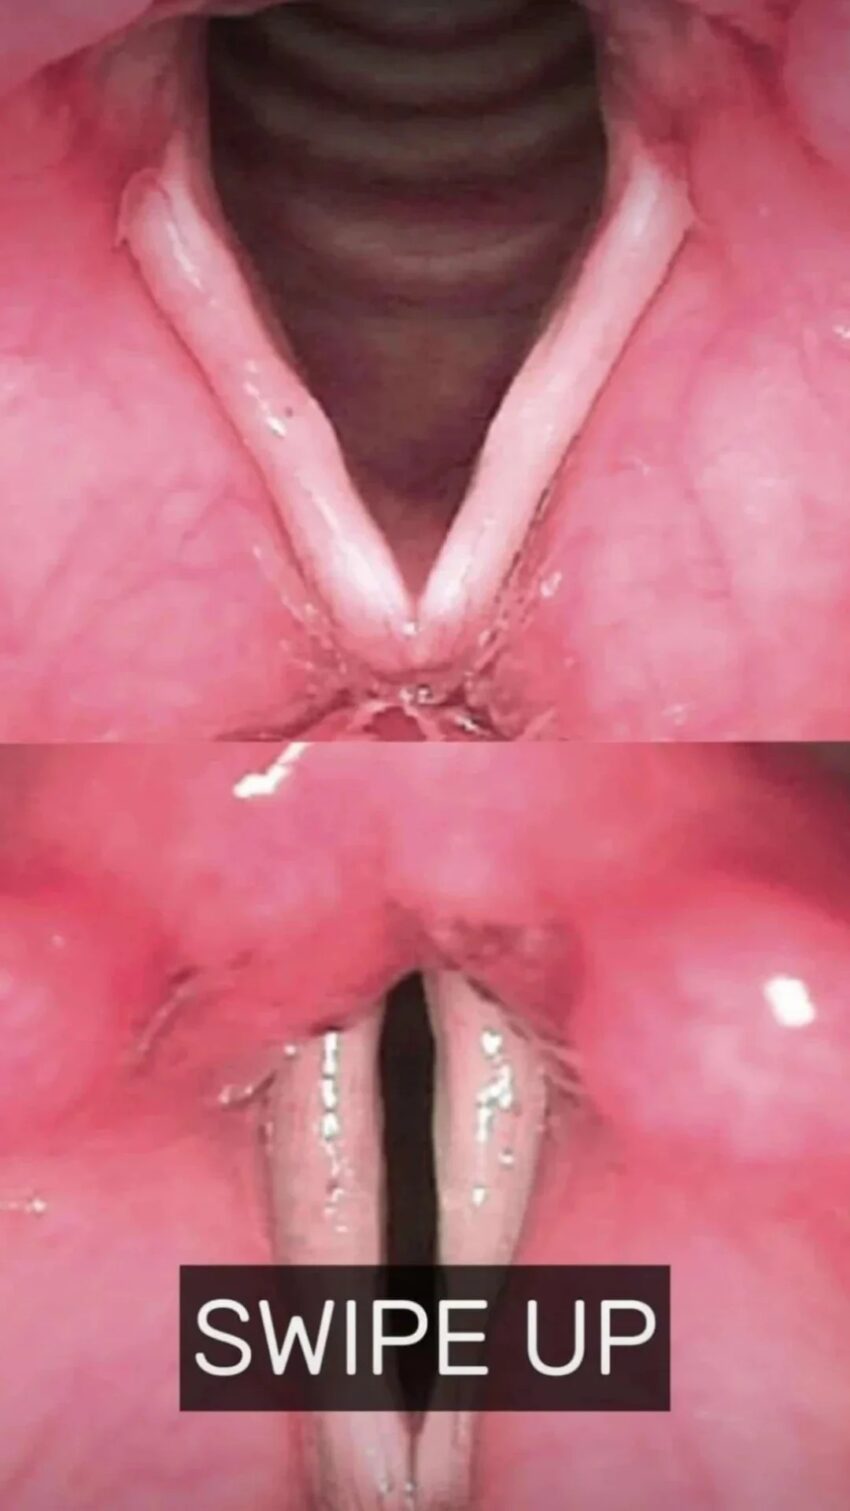

The causes, symptoms, and treatment of vocal cord nodules

Vocal cord nodules

or “Singer’s nodules,” are benign growths from vocal strain, causing hoarseness and pitch issues in children. Diagnosis uses laryngoscopy and stroboscopy, while treatment focuses on voice therapy, hydration, and managing reflux. Children usually recover with therapy; severe adult cases may require surgery. Progress is reviewed after three months.